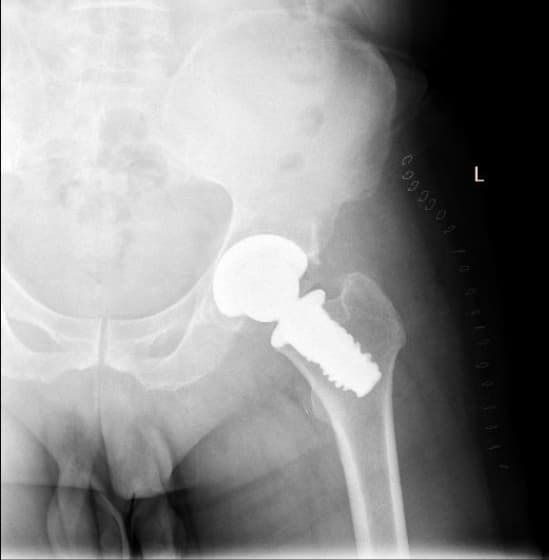

Дунд чөмөгний дээд хэсгийн /проксималь/ хавдар

Дунд чөмөгний проксималь буюу дээд хэсгийг хамарсан яс, зөөлөн эдийн гаралтай хавдрын улмаас түнхний үе, дунд чөмөгний дээд хэсгийг бүхлээр нь солих (мөч хадгалах мэс засал) мэс заслын эмчилгээг хийнэ.

Мэс заслын өмнөх болон дараах рентген зураг